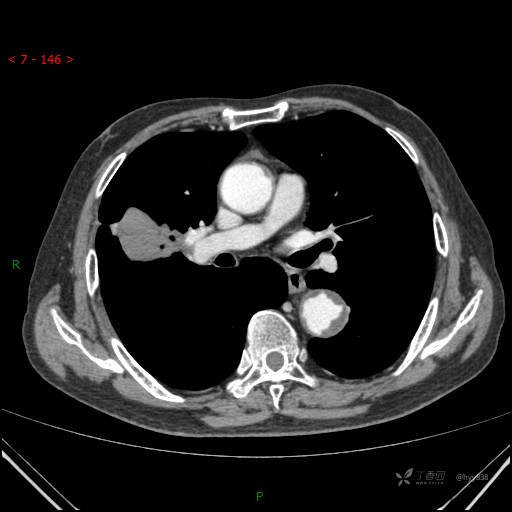

胸部CT肺窗

增强动脉期